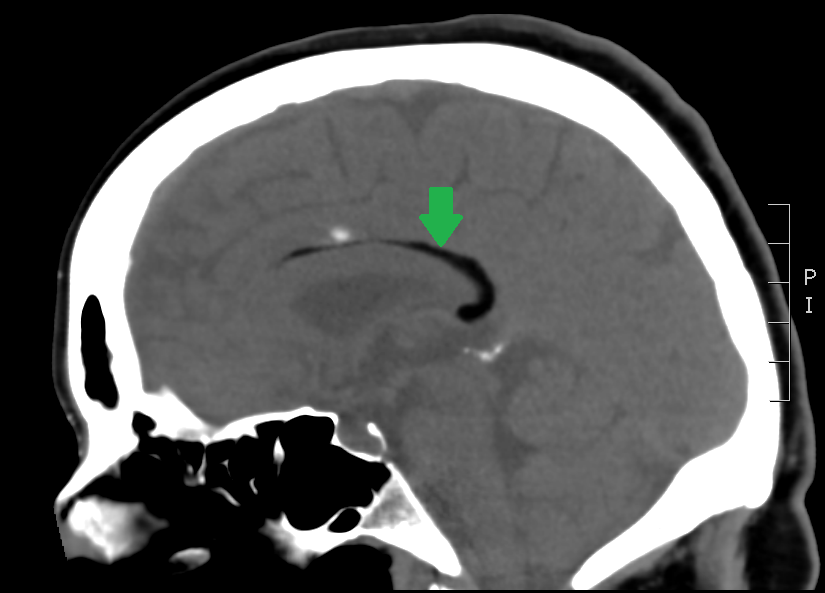

All three images above are non-enhanced head CT’s. First, locate the lesion – it is highlighted by a green arrow in the saggital, and by a blue arrow with bone windowing in the axial imaging. Where is it? What is the density compared to the surrounding brain tissue and CSF? Given the density, what should be in your differential diagnosis?

The most likely structure identified by the green and blue arrows here is:

The answer is B) this is a lipoma. Only fat and air have a density below that of CSF on head CT. Although both lipomas and free air can look similar on normal brain windowing, by adjusting the image settings to bone windowing (middle image with blue arrow above), you will see that the lipoma is no longer totally dark.

Lipomas are relatively common, benign fatty tumors. They tend to be in the midline, just like this one is. They are usually developmental and rarely cause problems later in life – most of the time they are incidental findings like in this case. If large, they can disrupt the development of midline structures like the corpus callosum.